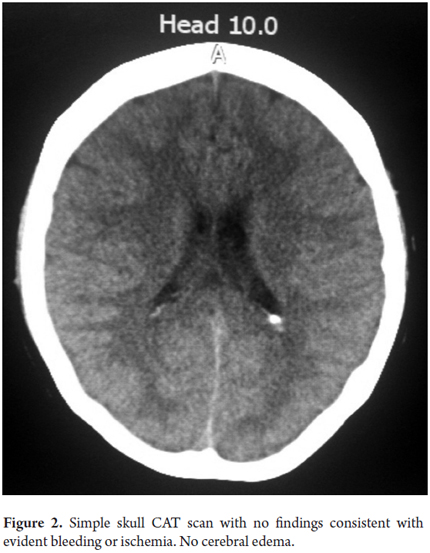

On the fourth day the patient suffered overall deterioration to grade II hepatic encephalopathy. Management metronidazole, lactulose (to counter encephalopathy) and N-acetylcysteine to manage liver disease was begun. Arterial blood gases showed an elevated anion gap which was related to a high level of high metabolic acidosis due to liver failure (FiO2: 0.28, pH: 7.47, pCO2: 15, PO2: 48, HCO3: 10.9, SatO2: 86%). This was treated medically with bicarbonate of soda. The patient was moved to the intensive care unit for progression to hepatic encephalopathy grade III and hemodynamic deterioration requiring vasopressor support. She did not respond favorably, and on the 5th day she developed grade IV hepatic encephalopathy. Orotracheal intubation became necessary to protect respiration. A CT scan of her brain was taken (Figure 2) and appeared to be normal. The fundi of her eyes were without papilledema, but she was given a bolus of mannitol because of the possibility of intracranial hypertension. There was no clinical improvement. She developed supraventricular tachycardia and hemodynamic collapse requiring electrical and pharmacological cardioversion. She had also developed upper gastrointestinal bleeding for which infusion of omeprazole was initiated. She was transfused with 15 cc/kg of plasma plus vitamin K. The patient progressed to cardiac arrest. She was unresponsive to advanced maneuvers and died 5 days after admission to the institution and nine days after onset of symptoms. The cause of death was determined to be fulminant liver failure secondary to hepatitis B since other major studios required referrals to a hospital of greater complexity which were not possible to get in time because this is a state hospital.

Cerebral edema occurs most in the acute presentation of fulminant liver failure and is the leading cause of mortality in these patients. The first link in the management of these patients is to prevent and manage intracranial hypertension (ICH). For patients with Grade 1 and Grade 2 hepatic encephalopathy it is advisable to minimize stimuli and maintain the head elevated at 30°. For patients with Grades 3 and 4 of hepatic encephalopathy orotracheal intubation is, as in our patient, probably necessary. These patients most likely will be suffering from severe intracranial hypertension (ICP> 25 mm Hg for> 5 minutes, or ICP> 40 mm Hg, or cerebral perfusion pressure <40 mm Hg for more than two hours). Mannitol IV bolus at doses of 0.25 to 1.0 g/kg is recommended for these patients when the osmolarity is less than 320 mOsm/L (1). This was administered to patient, despite our inability to monitor intracranial pressure.